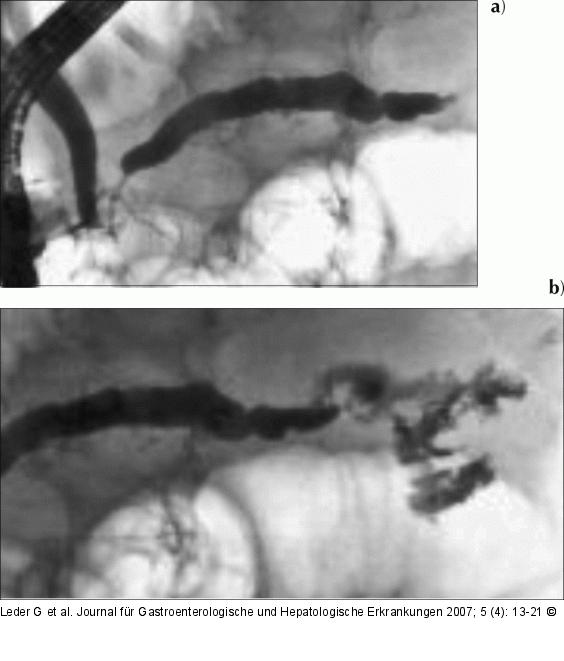

Abbildung 3: Chronische Pankreatitis a) Die ERCP vom 13.7.2005 zeigt via die Minorpapille die mittlerweile deutlichere Einengung des Ductus Santorini im Bereich des Pankreaskopfes und den konsekutiven Gangaufstau des Hauptganges (Ductus Wirsungianus). b) Bei weiterem Anspritzen des Ganges tritt Kontrastmittel in die später intraoperativ als nekrosehaltig identifizierte Pseudozyste über. |

Abbildung 3: Chronische Pankreatitis

a) Die ERCP vom 13.7.2005 zeigt via die Minorpapille die mittlerweile deutlichere Einengung des Ductus Santorini im Bereich des Pankreaskopfes und den konsekutiven Gangaufstau des Hauptganges (Ductus Wirsungianus). b) Bei weiterem Anspritzen des Ganges tritt Kontrastmittel in die später intraoperativ als nekrosehaltig identifizierte Pseudozyste über. |